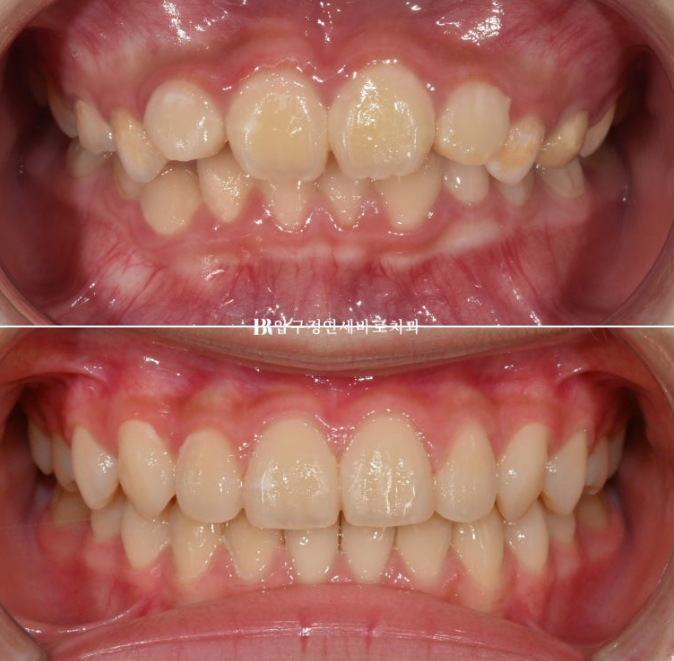

전 후 비교 사진 보겠습니다.

2022.09~2024.09

중심선은 잘 맞았고 앞니가 깊게 물리는 과개교합도 개선이 되었습니다.

파란 화살표 부분을 자세히 보시면 가운데 앞니 모양이 바뀐 것이 보입니다.

사진에서 보이듯 항아리 모양 치아는 앞니가 잘 배열이 된 후에도 여전히 끝단이 벌어져 보입니다.